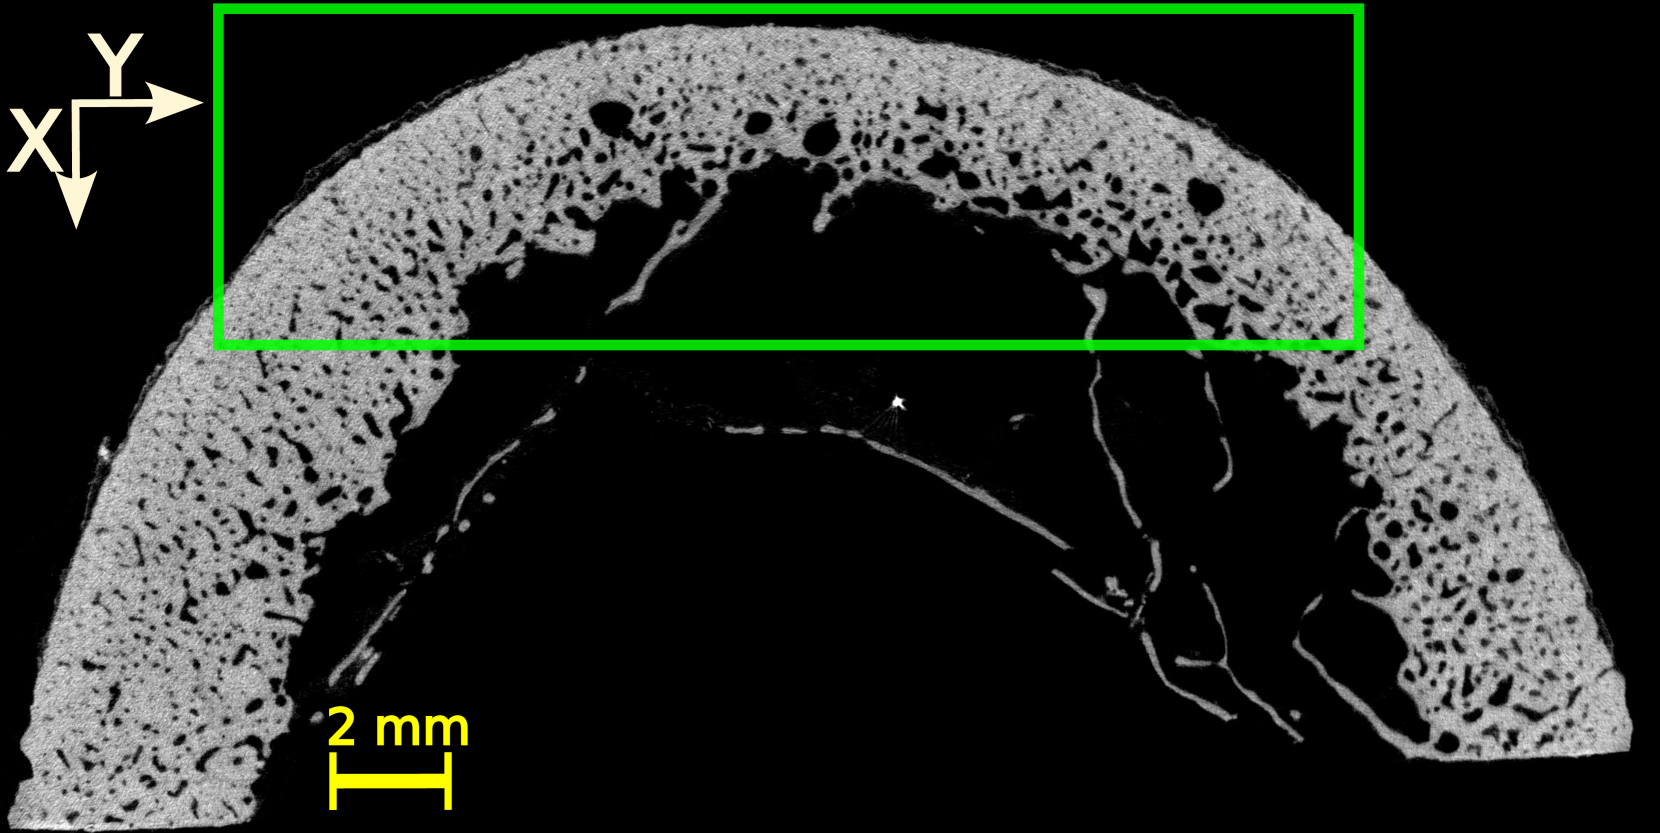

Four volumes of interest (VOI) were defined within the three-dimensional (3D) HR-µCT image of each sample. The thickness (direction of the bone axis) and width of the VOIs were 15 and 20 mm, respectively. The height of the VOIs varied between 8 and 10 mm, depending on the cortical thickness and diameter of each sample. Figure LABEL:method:example_xray_slice shows a two-dimensional (2D) slice in the transverse plane extracted from each VOI for all the samples. The VOI’s dimensions approximately correspond to the thickness (probe elevation direction), lateral dimension (probe aperture) and depth of the US image.

The initial step was to apply a Gaussian filter (round kernel of radius 2 or 3, depending on the sample) to remove acquisition noise. Then, the VOI were binarized using 3D Otsu method [31]. Given that this study focuses on the cortical bone tissue, we removed, in the endosteal region, the bone remnants resulting from a trabecularization [5] of the cortex (samples 4 and 5, see Figure LABEL:method:example_xray_slice and Figure S1 in supplementary materials). To do this, we used kernel filtering (either Kuwahara or Uniform kernels with a radius of 2) and morphological operations to close all pores below a specific threshold diameters, thereby generating a mask that excluded trabecular regions. The specific choice of kernel and parameters varied across samples to accommodate the high morphological variability among the samples (Figure LABEL:method:example_xray_slice).

An average cortical thickness was measured for each volume of interest (VOI), yielding four thickness values per sample, using Matlab 2023b (Mathworks Inc., Natick, MA, USA). The procedure was as follows: (i) The pores in the binarized 2D images were closed; (ii) the resulting images in a VOI were averaged to produce a single 2D image representative of the VOI (Figure 2) ; (iii) the average image was binarized using Otsu method ; (iv) the contours of the outer surface (periosteal) and inner surface (endosteal) were detected (Figure 2) and approximated by parabolas; and (v) a ’median’ line was determined at mid-distance from the two parabolas. Finally, cortical thickness was calculated for each region of interest as the ratio between the bone surface to the length of the median line. The average cortical thickness derived through this method will be compared to the cortical thickness measured with US.

The 20 VOIs (4 VOIs in each of the 5 samples) showed a great diversity in terms of cortical thickness, porosity, and distribution of pores (Figure LABEL:method:example_xray_slice). Cortical thickness estimated from micro-CT images ranged from 2.5 to 6.3 mm (Table LABEL:table_chap_4:pore_stat_samples_combined). The microstructure parameters are summarized in Table LABEL:table_chap_4:pore_stat_samples_combined. Samples 1 and 2 had the lowest porosity (5–6.4 % and 5.3–6.7 %, respectively) and no large pores (Lg.Po.Dm 175 m). Sample 3 showed moderate porosity (7–12.3 %) with moderately large pores (Lg.Po.Dm in the range 224–228 m). Samples 4 and 5 presented the highest porosity (12.2–16 % and 16.4–16.6 %, respectively) with 10% of the pores with diameter above 300 m. Sample 4 displayed the largest pores (Lg.Po.Dm in the ranged 334–423 m), which can be clearly seen in Figure LABEL:method:example_xray_slice. Porosity values and the porosity gradient from the periosteal to the endosteal surface seen in some samples are consistent with the literature data for elderly donors [27].